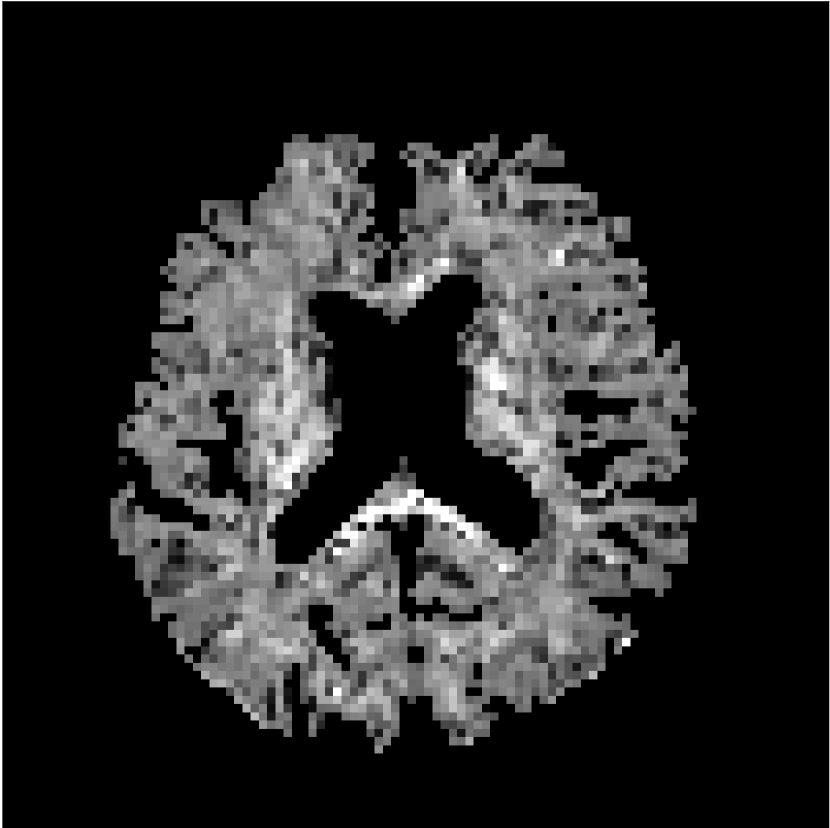

Figure 8 shows examples of non-diffusion-weighted images before and after processing. The raw images (Raw) served as the input for the magnitude deep learning (MCNN) and complex deep learning (CCNN) methods.

Raw 𝐱tsubscript𝐱𝑡\mathbf{x}_{t}

MCNN, fθ^(𝐱t)subscript𝑓^𝜃subscript𝐱𝑡f_{\hat{\theta}}\left(\mathbf{x}_{t}\right)

MCNN Resid., Ric(𝐱t)fθ^(𝐱t)Ricsubscript𝐱𝑡subscript𝑓^𝜃subscript𝐱𝑡\text{Ric}(\mathbf{x}_{t})-f_{\hat{\theta}}\left(\mathbf{x}_{t}\right)

CCNN, fθ^(𝐱t)subscript𝑓^𝜃subscript𝐱𝑡f_{\hat{\theta}}\left(\mathbf{x}_{t}\right)

CCNN Resid., Ric(𝐱t)fθ^(𝐱t)Ricsubscript𝐱𝑡subscript𝑓^𝜃subscript𝐱𝑡\text{Ric}(\mathbf{x}_{t})-f_{\hat{\theta}}\left(\mathbf{x}_{t}\right)

No PF

5/8 PF

Figure 8: Examples of non-diffusion-weighted images from in vivo data at b=0𝑏0b=0 s/mm2. Artifacts in the Raw image, 𝐱tsubscript𝐱𝑡\mathbf{x}_{t}, are corrected by the MCNN and CCNN models, fθ^(𝐱t)subscript𝑓^𝜃subscript𝐱𝑡f_{\hat{\theta}}(\mathbf{x}_{t}). Also shown are the residuals between the CNN corrections and the original Raw image with Rician bias correction Ric(𝐱t)Ricsubscript𝐱𝑡\text{Ric}(\mathbf{x}_{t}) [10]. The Gibbs artifacts removed by the methods are observed in the residuals. The MCNN method introduces some banding artifacts at the PF 5/8ths factor that are not present in the CCNN method.

Both methods remove artifacts, but the MCNN method allows residual rippling artifacts to pass through in the presence of partial Fourier. These rippling artifacts are not present in the CCNN method.